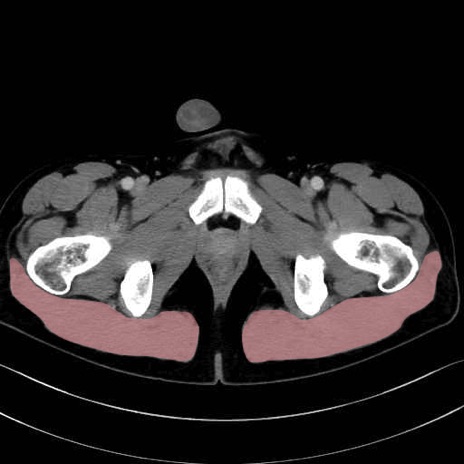

3. 殿部の筋肉(表層・中層・深層)

大殿筋 (Gluteus maximus)

中殿筋 (Gluteus medius)

小殿筋 (Gluteus minimus)